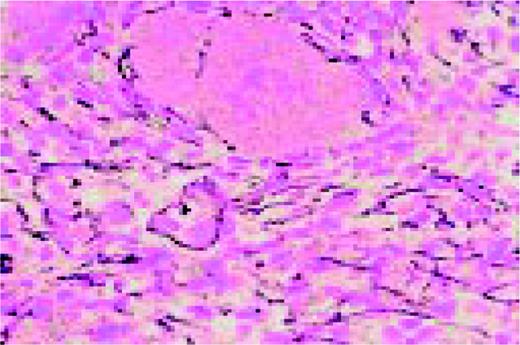

Amyloid, bone marrow biopsy, H&E stain. A small blood vessel is heavily infiltrated with the pink-staining, waxy amyloid material.FIG48

Slide L49